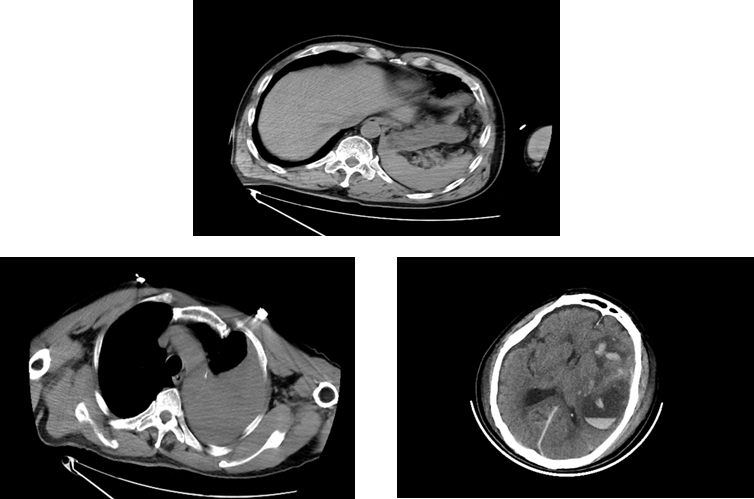

120急救车将居先生(化名)送至我院抢救室时,情况已经万分危急,时间就是生命!急诊抢救室团队立即启动应急预案,心电监护、吸氧、建立静脉通道、床边超声FAST筛查等抢救措施一气呵成。全身CT扫描提示患者全身上下存在颅脑、胸腔、腹腔等多处致命损伤。

面对如此复杂危重的病情,苏大附四院创伤中心立即激活多学科会诊(MDT)机制,神经外科、普外科、胸外科、血管外科与介入科等多个科室专家迅速集结抢救室。多学科专家团队迅速对患者病情进行了精准评估:患者遭受活动性大出血和创伤性凝血病威胁,并且膈肌破裂引起胸腔压迫,必须立即手术!